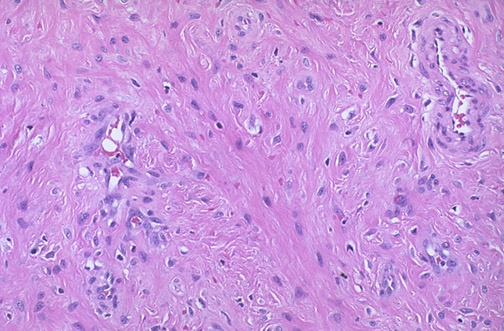

This nasal angiofibroma is benign, but can block the nasal passages, erode adjacent structures, ulcerate, and bleed. The fibrous stroma has plump fibroblastic cells along with scattered capillaries.